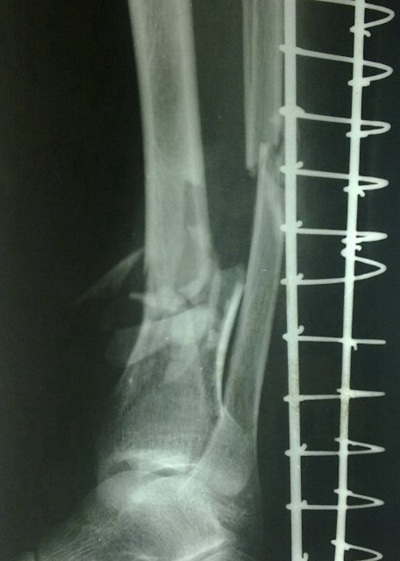

骨折圖片